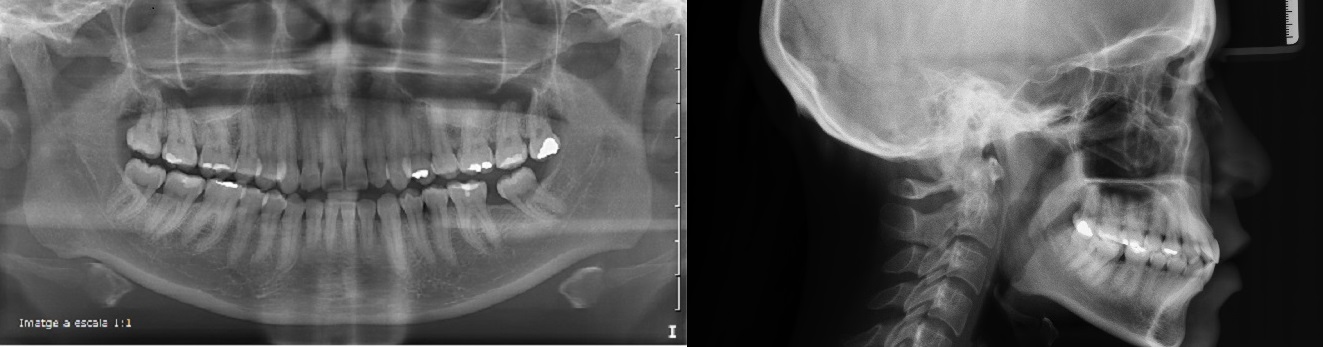

Caso de paciente que presenta una Clase III modida cruzada anterior, arcada estrecha y apiñamiento.

Clinica Mariana sacoto Navia expertos Ortodoncia Invisalign Barcelona

Paciente anterior clase III mordida cruzada, imágenes de su boca después de 10 meses de tratamiento, esta en la fase final.